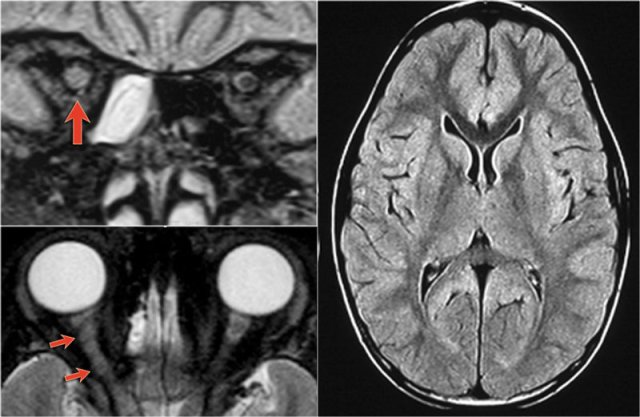

Brain lesions in NMO

Previously it was thought that in NMO the brain was spared, but now we know, that brain lesions do occur.

They are often distinct from those seen in MS.

In Asia 60-80% of patients with NMO have brain abnormalities.

In Europe only 25-40%.

The location of the brain lesions in NMO is only around the ventricles.

The reason why these brain lesions are located around the ventricles is the following:

The NMO IgG auto-antibodies are directed against Aquaporin-4 water-channels.

So just like sodium- and potassium channels in the cells, there are also water-channels.

The highest concentration of these Aquaporin-4 water-channels is seen around the ventricles.

The images show abnormal signal around the third and frontal horns of the lateral ventricles.

Things become even more complicated, since it is also possible to have large lesions in the corpus callosum of patients with NMO as was described by Nakamura (6).

So in any CNS disease with optic nerve and spinal cord involvement it is goos to do the test for NMO-IgG.